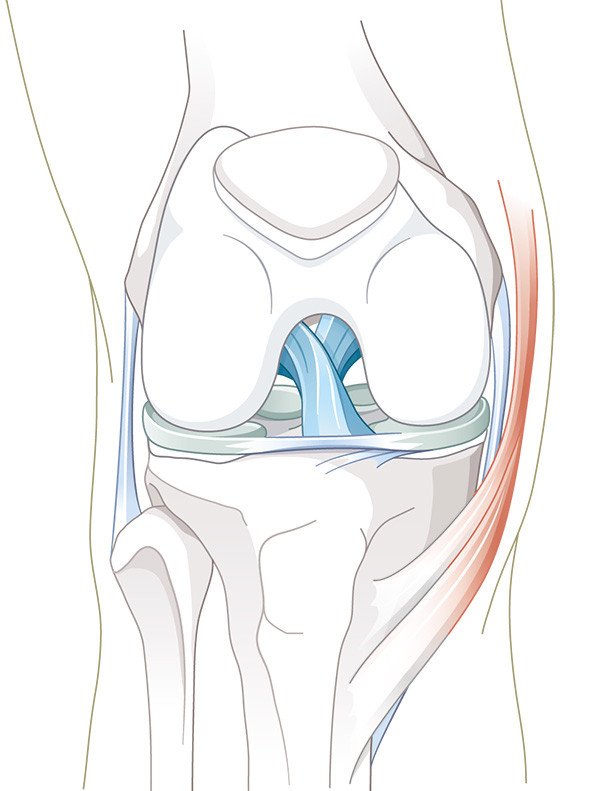

Der Gelenkknorpel (artikulärer Knorpel oder hyaliner Knorpel) umkleidet die Enden aller langen Röhrenknochen in unserem Körper. Beim Aufeinandertreffen von Röhrenknochen auf Röhrenknochen bildet sich zwischen diesen ein Gelenk als abgeschlossene Funktionseinheit. So verbindet das Kniegelenk bspw. in Gelenk-Funktion den Oberschenkel mit dem Unterschenkel und erlaubt uns die tägliche Fortbewegung oder sportliche Aktivität. Der artikuläre Knorpel erlaubt dabei eine eigentlich unlimitierte reibungsfrei stossdämpfende Funktion, so dass wir uns bis ins höhere Alter schmerzfrei ohne Abnützung bewegen können. Er schützt den unterliegenden Knochen, welcher in unserem Körper primär als Stützskelett dient und diese überliegende Schutzschicht benötigt. Dabei leistet der Knorpel biomechanische Höchstleistungen und ist dazu in der Lage, Spitzendruckkräfte von bis zum 25-fachen unseres Körpergewichts auszuhalten ohne strukturelle Schäden davonzutragen.